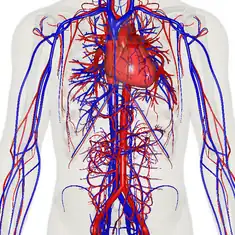

![]() The human circulatory system (simplified). Red indicates oxygenated blood carried in arteries. Blue indicates deoxygenated blood carried in veins. Capillaries, which join the arteries and veins, and the lymphatic vessels are not shown. | |

The circulatory system, also called the cardiovascular system or the vascular system, is an organ system that permits blood to circulate and transport nutrients (such as amino acids and electrolytes), oxygen, carbon dioxide, hormones, and blood cells to and from the cells in the body to provide nourishment and help in fighting diseases, stabilize temperature and pH, and maintain homeostasis.

The essential components of the human cardiovascular system are the heart, blood and blood vessels.[6] It includes the pulmonary circulation, a "loop" through the lungs where blood is oxygenated; and the systemic circulation, a "loop" through the rest of the body to provide oxygenated blood. The systemic circulation can also be seen to function in two parts – a macrocirculation and a microcirculation. An average adult contains five to six quarts (roughly 4.7 to 5.7 liters) of blood, accounting for approximately 7% of their total body weight.[7] Blood consists of plasma, red blood cells, white blood cells, and platelets. Also, the digestive system works with the circulatory system to provide the nutrients the system needs to keep the heart pumping.[8]